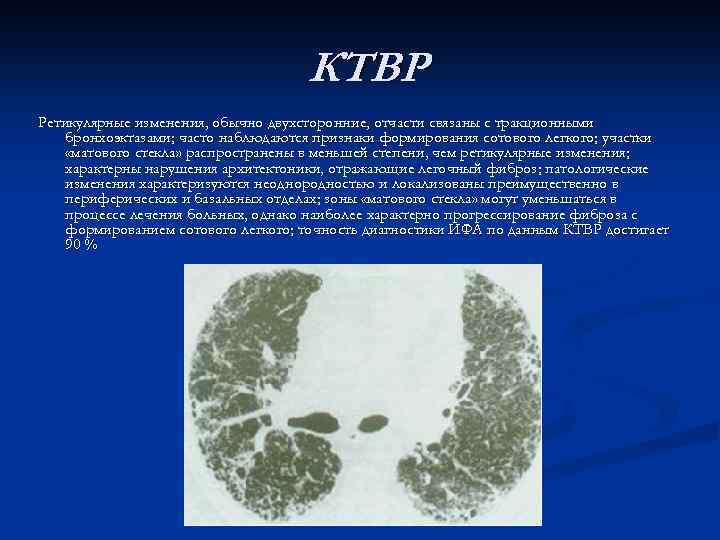

КТВР Ретикулярные изменения, обычно двухсторонние, отчасти связаны с тракционными бронхоэктазами; часто наблюдаются признаки формирования сотового легкого; участки «матового стекла» распространены в меньшей степени, чем ретикулярные изменения; характерны нарушения архитектоники, отражающие легочный фиброз; патологические изменения характеризуются неоднородностью и локализованы преимущественно в периферических и базальных отделах; зоны «матового стекла» могут уменьшаться в процессе лечения больных, однако наиболее характерно прогрессирование фиброза с формированием сотового легкого; точность диагностики ИФА по данным КТВР достигает 90 %